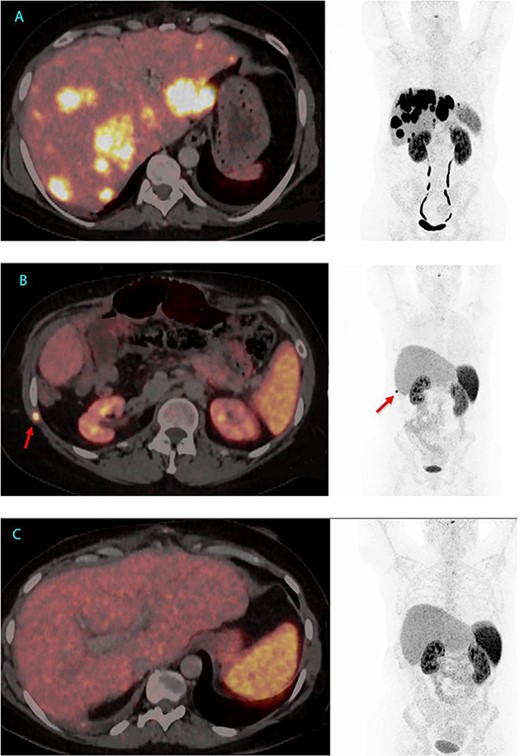

Given her declining health, the patient was placed on the LT waitlist in March 2022. After a 7-month hospital stay, she underwent an LT in June 2022. Figure 1 presents the final 64Cu-DOTATATE PET/CT prior to transplantation, demonstrating extensive hepatic involvement without extrahepatic metastases. The LT was a technical demanding and high-risk procedure because of the previous Whipple procedure, liver resections and complicated biliary leakages. Abdominal wall was closed POD 2 with a biological mesh. The transplantation was complicated by necrotizing pancreatitis, successfully treated by endoscopic, transgastric necrosectomy.

64Cu-DOTATATE PET/CT from 2 June 2022, 7 weeks before LT with extensive hepatic involvement but no extrahepatic metastases (A). 64Cu-DOTATATE PET/CT 15 months after LT revealed an implantation metastasis in the thoracic wall (B). Latest 64Cu-DOTATATE PET/CT performed 18 months after LT and 3 months after resection of the thoracic metastasis showed no signs of recurrence (C).

After LT, plasma VIP normalized, but the patient was hospitalized for an additional 4 months for rehabilitation and treatment of different infections. In November 2023, 15 months after LT a routine 64Cu-DOTATATE PET/CT revealed a potential implantation metastasis in the thoracic wall where a drain had previous been placed. Surgery was conducted and pathological examination confirmed the presence of a NET metastasis with a Ki-67 index of 10%.

In the most recent 64Cu-DOTATATE PET/CT scan from January 2024, conducted 18 months after LT, there was no signs of recurrence. Currently, the patient is in good health, has started part-time work and has no hormone-related symptoms, since LT serum VIP has been below level of detection (<3.8 pmol/L) (Figs 1 and 2).